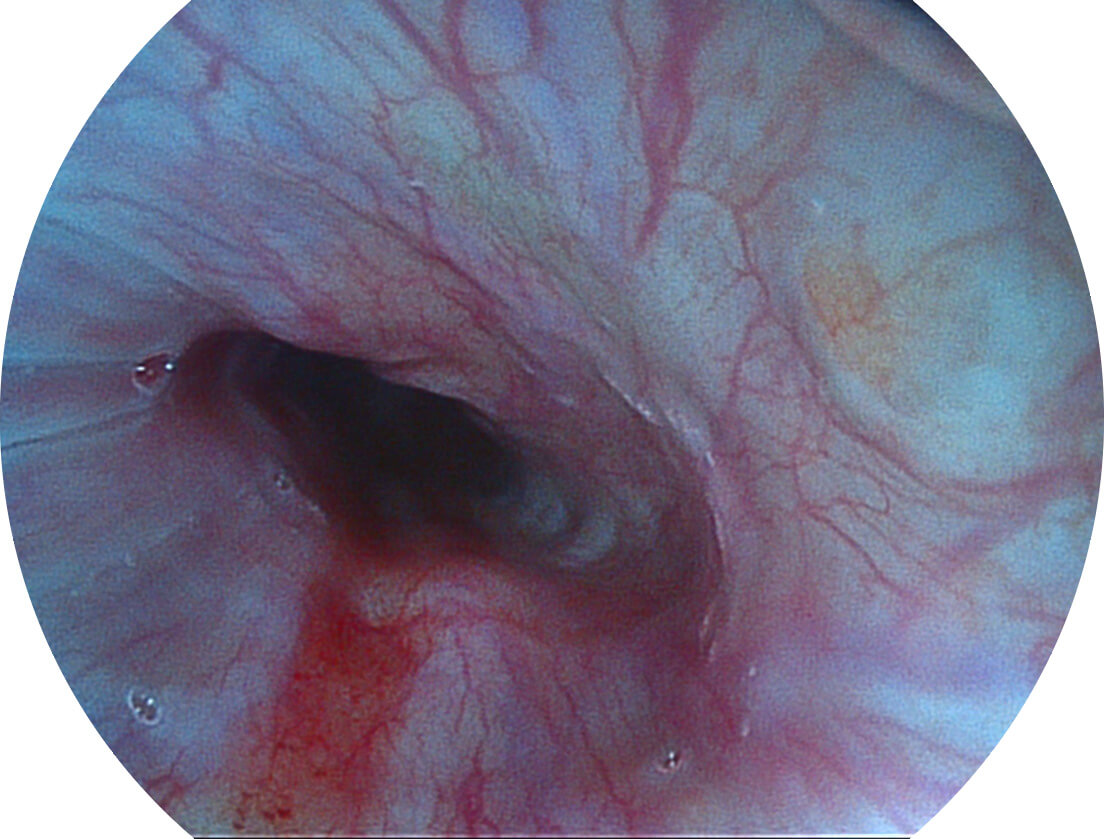

图像具有高亮度、高黏膜血管颜色对比度的特点,且不改变粘液、食物残渣、粪便的基本颜色,可在中远景下进行观察,助力消化道早期疾病的诊断。

• 白光图像 SFI图像